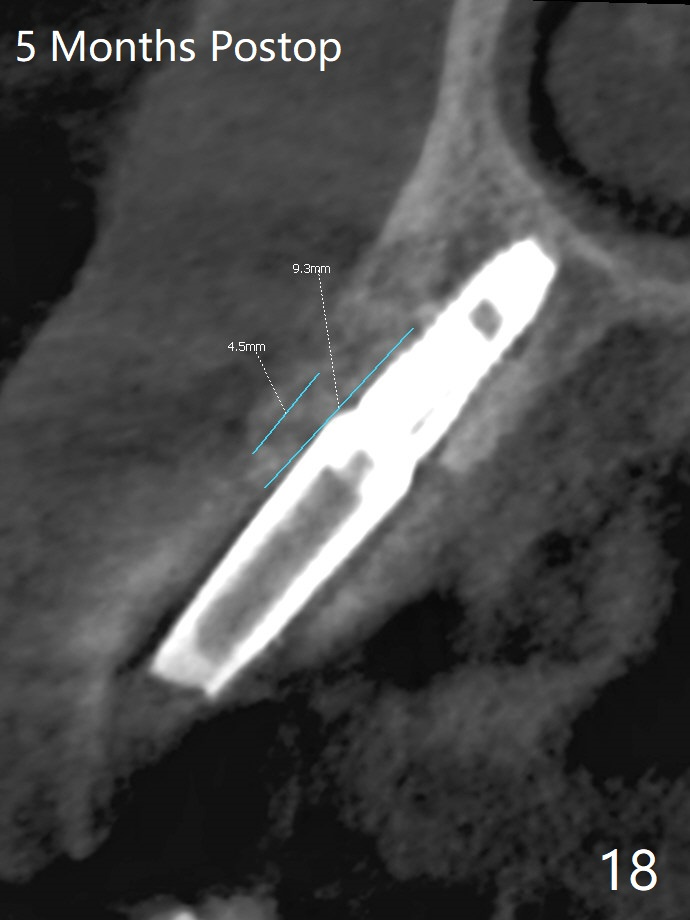

A 62-year-old man with generalized chronic periodontitis returns with chief complaint of loose tooth at #11 (Fig.1). Although a buccal fistula (Fig.1 <) is closer to #12 than to #11, percussion is more severe at #11 than 12. The buccal plate of #11 is missing, but it is possible to place a narrow immediate implant because of the wide alveolus (Fig.2). Since the gingiva is ~ 10 mm long, a mill abutment is to be used (Fig.3,5). In fact the fistula communicates with #11 extraction socket. After debridement, osteotomy is initiated (Fig.4) for a 3.8x10 mm implant ~ 35 Ncm, followed by seating a 4.5x2 mm mill abutment (Fig.5). Abundant sticky bone is placed in the remaining socket (for buccal plate reconstruction) and against the root surface of the neighboring teeth (Fig. 6 * (#10,12)). Finally 2 pieces of PRF membranes are utilized to facilitate repair of the buccal soft tissue defect (Fig.7 *). The root prominence of the canine seems to be maintained by the bone graft (Fig.8 C). Acrylic dressing holding the PRF membranes in place remains in situ with the healthy gingiva buccal (Fig.9) and palatal (Fig.10) 11 days postop. Note the acrylic locking into the undercuts of the neighboring teeth (*). 经过一段摸索发现离心每分钟1500转5分钟后,抽取上清液,接着再离心10分钟剩余上清液就形成血小板块,压制后便是血小板膜,后者似乎有助于软组织愈合,而上清液用来制备骨块,帮助硬组织生长。利用这个原则讨论以下病例治疗。The gingival margin gains ~ 5 mm 6 weeks postop when the acrylic dressing is removed (Fig.11,12 (<: previous one), as compared to Fig.7,8). 治疗结束时尖牙牙龈缘高于第一双尖牙(图七,八),六个星期后,尖牙牙龈缘却低于双尖牙(图十一,十二(箭头:原始牙龈缘))。术后2.5,4.5月基台周围牙龈似乎能与钛合金附着,防止细菌进入深部植体(图十三,十四)。临时牙冠脱落多次,可能与mill abutment太光滑有关,所以颊侧,舌侧磨成平面(图十四)。取模时好像不必取出基台清洗(仿佛没有炎症),原位用树脂延长基台。术后5个月CT显示颊侧骨板再生(图十六-十八)。取模时并没有用树脂加长基台;粘固时,牙冠颜色理想,但是照片中并不是如此(图十九,二十),颊侧骨板没有塌陷。术后11个月基台颊侧骨板没有萎缩(图二十一:B);3d图像:骨壁完全形成(图十六对比:部分形成)。密度也增高(图二十二:B),与术后五个月比较(图十七)。术后十一个月,粘固后五个月角化龈存在(图二十三),牙冠颈部有金属颜色透出,是因为二段式基台太粗了(最细4.5毫米),可以请实验室在牙冠内部涂opaque material而减轻。